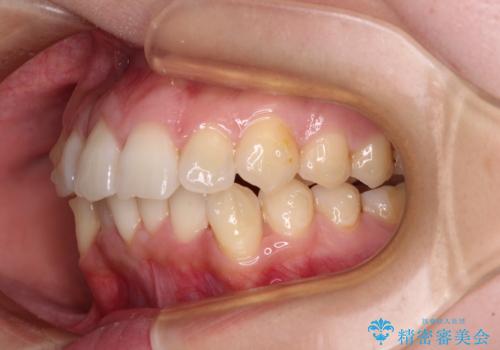

- 前歯のデコボコで前方に出ていることを気にして来院された患者様です。

上顎前歯が捻れて前方に飛び出しており、下顎前歯もそれに沿うようにデコボコとなっていました。

IPR(歯と歯の間を削る処置)によりスペースを獲得して上下顎前歯のデコボコを改善し、飛び出している前歯が引っ込むように設定し、インビザラインにて矯正治療を行うこととしました。